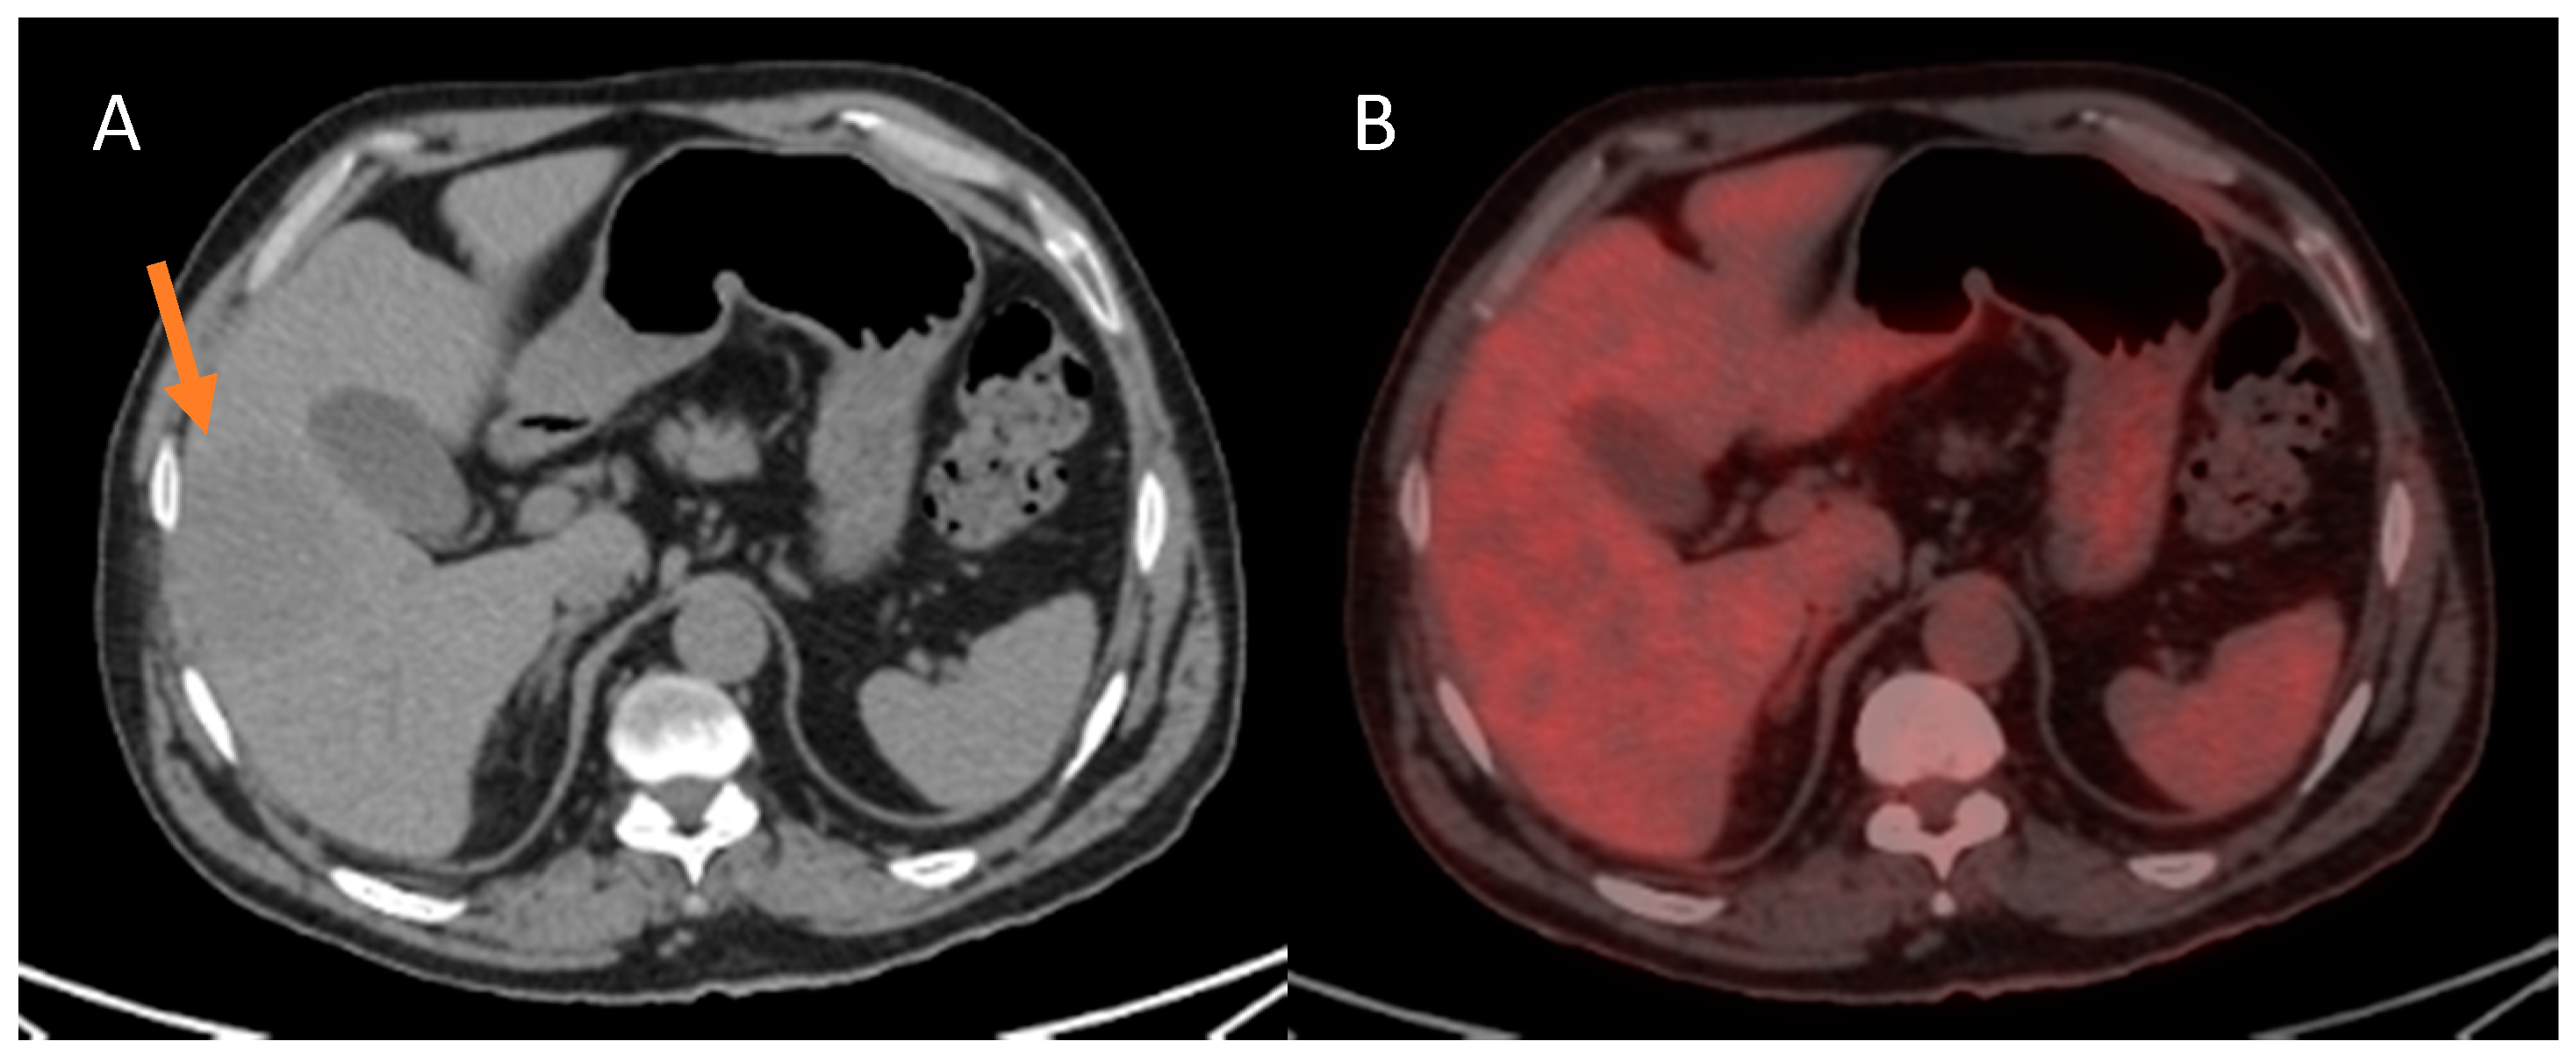

3.3.2. Poor Cellular Differentiation